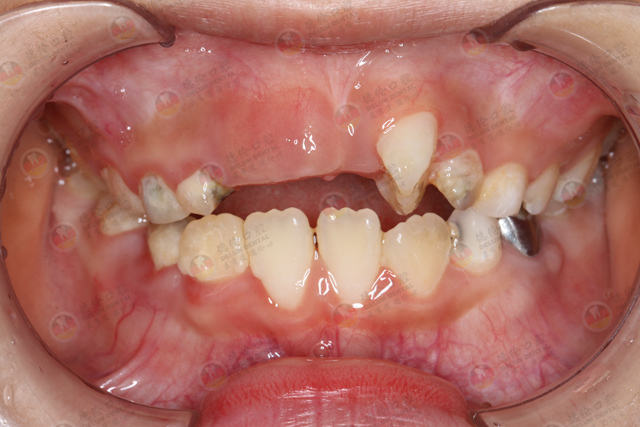

但是常见有部分宝宝,由于龋齿或者其他外伤而导致乳牙过早脱落或拔除。妈妈们对这种情况不以为然,认为乳牙迟早都是要换的,早掉晚掉没关系。但实际上,你正在毁掉孩子的口腔健康。乳牙早失影响的不仅仅是缺掉的这颗乳牙,还会给口腔带来更严重的问题。

虽然儿童的乳牙迟早要替换,但是它有一个自然规律,如果因为乳牙龋坏、意外损伤、炎症等原因,引起乳牙牙根缺失和乳牙早失,将会出现一系列更严重的问题。

每一颗乳牙的牙根下面都有恒牙的牙胚,同时乳牙对恒牙起到一个向导的作用。乳牙早失会使恒牙“迷失方向”,长得歪歪斜斜的。并且由于没有了乳牙的“阻力限制”,恒牙可能会过早萌出。

而这种“提前上岗”的恒牙的牙根通常处于未发育完善的状态,这也是日后恒牙容易脱落的原因。

影响牙生长

乳牙早失而恒牙还没有萌出,空缺位久了,旁边的牙齿就会向空缺位倾斜,对应牙也会伸长,影响邻牙和咬合功能。

随着邻牙倾斜程度的加强,原本恒牙萌出的位置间隙变小,使恒牙没有足够的正常空间顺利萌出,只好“另辟蹊径”,导致牙列畸形、牙列拥挤、咬合关系不良等后果。